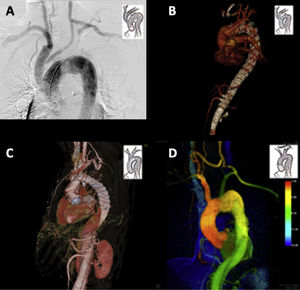

La RHA es un procedimiento especialmente atractivo en pacientes de alto riesgo que podrían no tolerar tiempos prolongados de circulación extracorpórea, parada circulatoria e hipotermia o reconstrucciones extensas en varias fases. Afortunadamente, hoy en día contamos con variantes técnicas reproducibles y factibles para la práctica totalidad de escenarios clínicos y variantes anatómicas de la patología de arco aórtico como mostramos en los ejemplos de la figura 1 operados en el Complejo Hospitalario Universitario de A Coruña.

Ejemplos de diferentes tipos de reparación híbrida de arco aórtico (RHA) realizadas en el Complejo Hospitalario Universitario de A Coruña. A.RHA tipo 1. Traslocación de tronco braquiocefálico (TBC) y arteria carótida común izquierda (ACCI) a aorta ascendente y bypass carótido-subclavio izquierdo con sellado endovascular de aneurisma fusiforme de arco aórtico mediante abordaje retrógrado sincrónico. B.RHA tipo 2. Sustitución de hemiarco y traslocación de TBC, ACCI y arteria subclavia izquierda a aorta ascendente y posterior tratamiento endovascular con endoprótesis fenestradas de aneurisma de arco aórtico y toraco-abdominal en un paciente con disección crónica tipo B. C.RHA tipo A. Reparación de aneurisma de arco y aorta torácica descendente en disección crónica tipo A en paciente con síndrome de Marfan mediante tubo valvulado mecánico y trompa de elefante congelada con Thoraflex™ Hybrid Ante-Flo™ (Vascutek-Terumo). D.RHA en zona 1. Paciente con aneurisma sacular de arco aórtico operada mediante bypass carótido-carótido retrofaríngeo y bypass carótido-subclavio izquierdo seguido de implante de endoprótesis NEXUS™ (Endospan Ltd/Jotec GmbH) con rama a TBC.